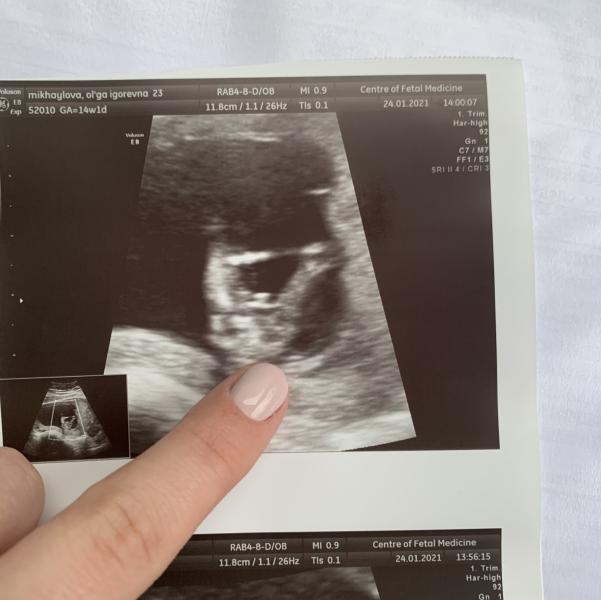

Девочки , привет! На первом скрининге, сказали мальчик) подскажите, из личного опыта, на сколько это вероятно?)) разные узи видела, всякое бывает

PS. Всем советую , кто из СПб, Центр Плода на Ваське, Медика